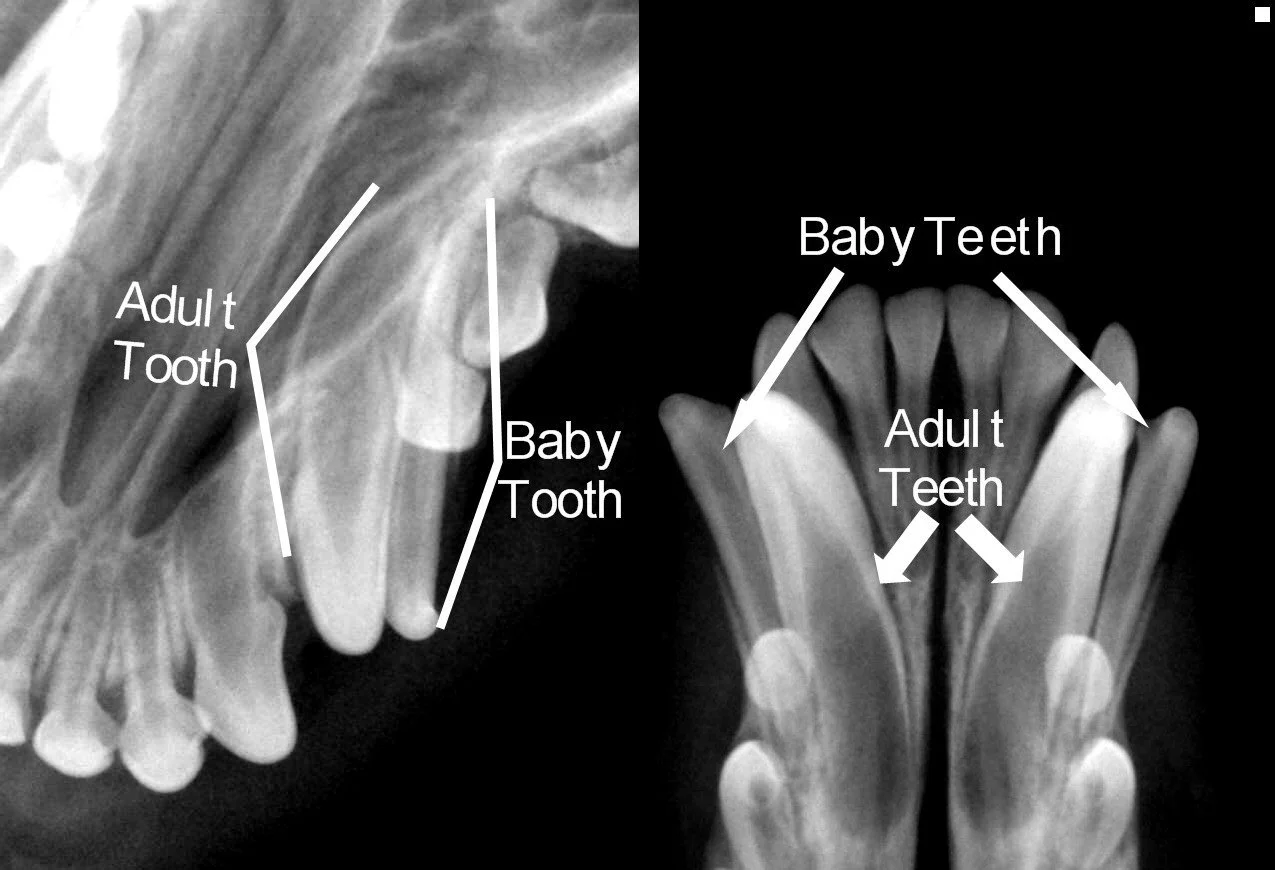

It is also not uncommon to find dental disease that is below the gumline and invisible with simple visual exams and cleanings, so to make sure severe disease is never left untreated we perform a full mouth set of dental x-rays along with every dental cleaning. We provide these x-rays at no additional charge.

Examples